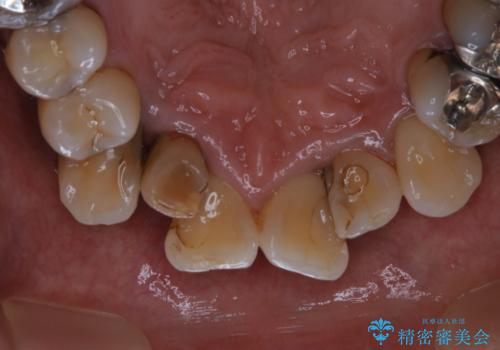

全体的な治療の開始前に着色取り